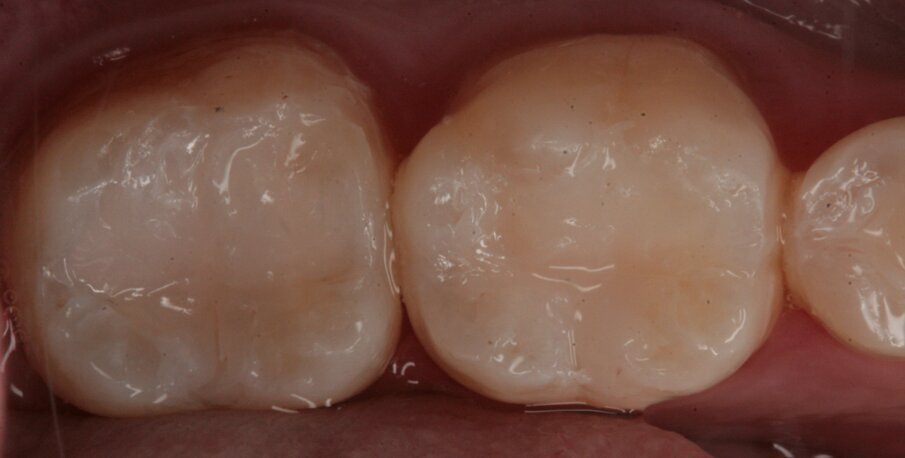

Si è proceduto alla ricostruzione diretta degli elementi 46, 45 e 44 mediante una massa di smalto e una di dentina (Figg. 23-27). L’elemento 47 è stato riabilitato mediante una ricostruzione indiretta in quanto il tessuto dentinale sano residuo era esiguo passando attraverso un build-up pre-protesico per esporre i margini sui quali alloggiare il manufatto (Fig. 28). Il restauro è stato realizzato in resina composita in quanto gli studi longitudinali dimostrano un ottimo follow-up a lungo termine (Fig. 29). La cementazione è avvenuta sempre con isolamento del campo operatorio facendo uso di un cemento duale (Fig. 30).

Fig. 23_Visione occlusale di 46 e 47.